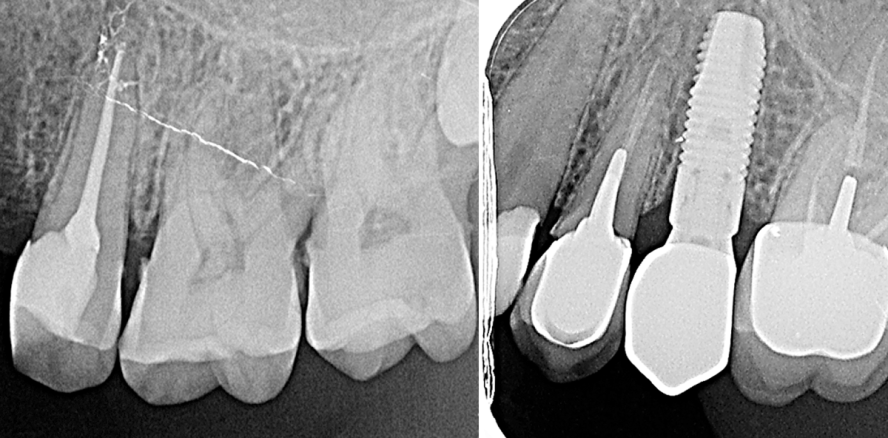

Bei tief zerstörten Zähnen werden die Zahnärzte heute vor die Wahl gestellt und müssen sich zwischen einer endodontischen Behandlung mit prothetischer Restauration und einer Ex­trak-tion mit anschließender Implantation entscheiden. Die Endodontologen ver­suchen aufgrund ihrer Spezialisierung in den meisten Fällen eine Erhaltungstherapie in Form einer komplexen endo­dontischen Behandlung (Abb. 1–3). Implantologen wählen hingegen oftmals den Weg der Extraktion und der frühzeitigen Implantation. Beide Wege sind möglich und können den Patienten auch langfristig zufriedenstellen, die Art der Behandlung sollte aber dennoch nicht vom Schwerpunkt des Kollegen abhängen – und genau darin liegt aus heutiger Sicht das Problem.

Die Endodontie rückt aufgrund ihrer zunehmenden Komplexität immer mehr in den Hintergrund der klinischen Tätigkeit. Die Gründe dafür liegen auf der Hand. Zum einen dauert eine ordentliche Wurzelbehandlung deutlich länger als die Insertion eines Implantats, denn der Erfolg wird maßgeblich von der Art und Weise der Dekontamination der Wurzelkanäle bestimmt. Zum anderen wird nach wie vor von einem „toten Zahn“ gesprochen und es wird bei der Implantation suggeriert, dass die Erfolgswahrscheinlichkeit deutlich über der einer Wurzelkanalbehandlung liegt. Vor einer Extraktion sollte jedoch nicht das Bauchgefühl oder die Forcierung von Implantaten durch die Industrie entscheiden, sondern einzig und allein die aktuelle Studienlage (Abb. 4 und 5).

Die direkte Extraktion eines infizierten oder tief zerstörten Zahns kann für den erfahrenen Implantologen mit deutlich weniger Risiken verbunden sein als eine lang andauernde und für den Patienten vielleicht kräftezehrende Wurzelbehandlung. Bei der einfachen Einzelzahnimplantation ist die Erfolgswahrscheinlichkeit sehr hoch und der Behandlungsaufwand für den Patienten sehr gering. Die langen Sessions mit ­Kofferdam und Mikroskop entfallen und der Patient verweilt seltener in der ­Praxis. Dies ist auch der Grund, warum die Implantologie einen hohen Stellenwert in der modernen Zahnmedizin hat und auch immer mehr haben wird. Einem Implantat folgt ein Zahn, der direkt ästhetisch in das Gesamtbild des Patienten passt – was im Anschluss an eine Wurzelkanalbehandlung nicht garantiert werden kann. Nicht selten müssen mit der Zeit verfärbte Zähne mit Vollkronen restauriert werden. Die Gesamtkosten der Endodontie können dabei schnell die Kosten der Implantologie übersteigen. Betrachtet man die Vor- und Nachteile aus der Sicht des schnellen Erfolgs für den Patienten, so erscheint die Implantologie in vielen Fällen als Therapie der Wahl (Abb. 9–12).